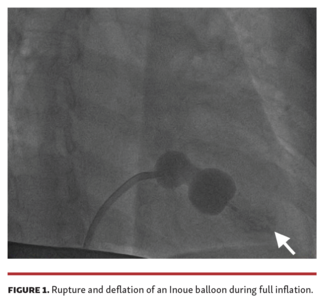

The reuse of sterilized Inoue catheters is a common cause of rupture. Proper meticulous inspection of reused Inoue balloons for deformity or leakage through the small holes is necessary to prevent such complications.